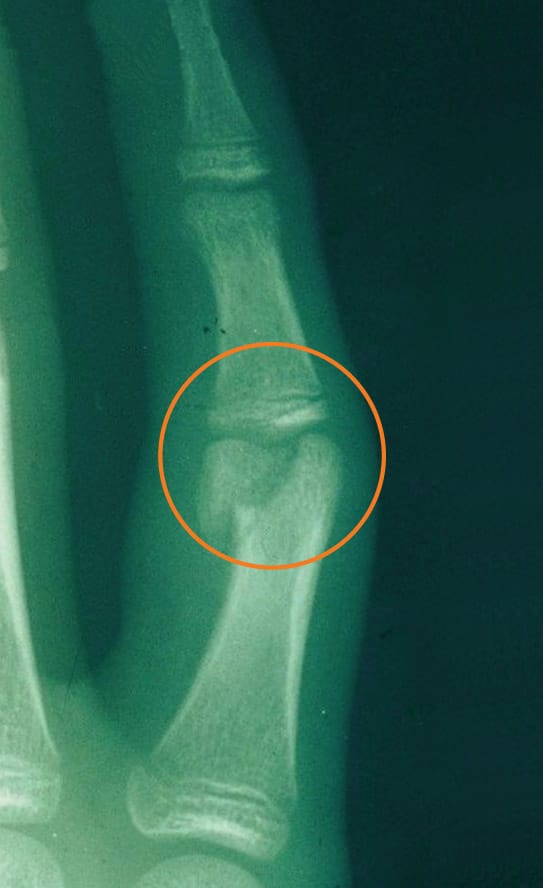

Fractures in children may be non-displaced, which means that it is a “hairline” fracture, or a fracture that has not broken into two separate pieces. Other fractures may be displaced, which means that it is a complete fracture that has broken into two or more pieces with some shift in position so that the ends of the broken bone are not in alignment (see Figure 1a). Fractures may occur in the shaft of the bone, or near the end, or in the joint.

Children are able to “remodel” (the specific process of bone resorption and formation) a broken bone after it heals and as the child grows. Certain breaks may not have to be re-aligned perfectly because of this ability to remodel with growth. Younger children have greater potential for remodeling with growth. Fractures with angulation in the same direction as joint motion (bending and straightening) also have greater potential to remodel. Fractures that disrupt the surface of a joint usually need to be realigned as precisely as possible, though, and may need surgery to do so (see Figure 2a). Fractures that are rotated or twisted, or angled out to the side also need to be realigned more precisely as they have less potential to remodel (see Figure 1a).